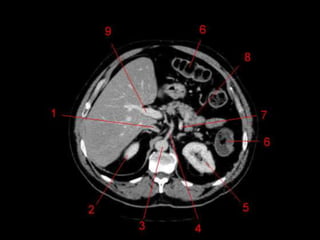

Subdivisão Funcional • Osoito segmentos são divididos: – A primeira divisão é realizada dividindo através da Porta Hepática, em esquerdo (I a IV) e direito (V a VIII) – A divisão é feita baseada em um relógio – Caudado é o segmento I – No ‘lobo’ esquerdo, o IV separa-se do II e do III pela veia hepática esquerda, representado anatomicamente pelo ligamento falciforme. – II e III se dividem através de uma linha imaginária transversal na altura da porta hepática. – No ‘lobo’ direito, se divide os segmentos através de uma linha transversal e pela veia hepática direita.

Subdivisão Funcional • Fundamentalimportância para Ressecção. • Maioria das lesões são do fígado direito.

Vasos Hepáticos • Veiaporta – Formada pela união da Veia Esplênica e Mesentérica Superior • Artéria Hepática – Segmento da Tronco Celíaco – Dividida em Comum e Própria pelo surgimento da artéria gastroduodenal. • Na maioria das pessoas, a artéria é anterior a veia (91%). Na maioria das pessoas, a artéria hepática direita passa atrás do ducto hepático comum. (64%)

Técnicas de Imagem •US: Primeiro exame pedido ao: 1) dor no hipocondrio direito; 2) testes de função hepáticas anormais; 3) suspeita de malignidade. • TC: Tres fases – Arterial (10 a 20 segundos) – Fase venosa portal ( 30 segundos ) – Fase venosa hepática (60 segundos) • TC Portografia: Metastases.